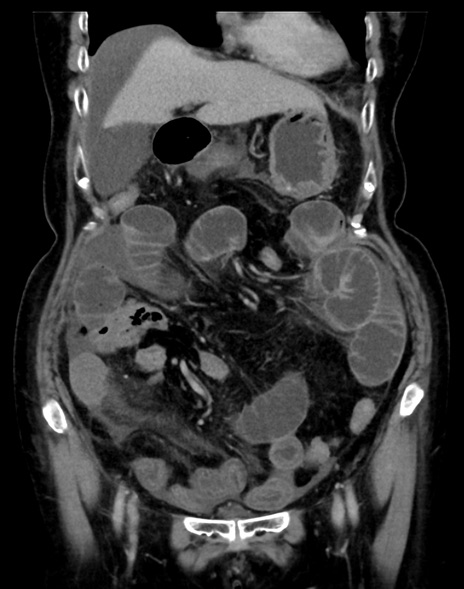

症例13 CT(冠状断像)1日半後

(横断像)1日半後